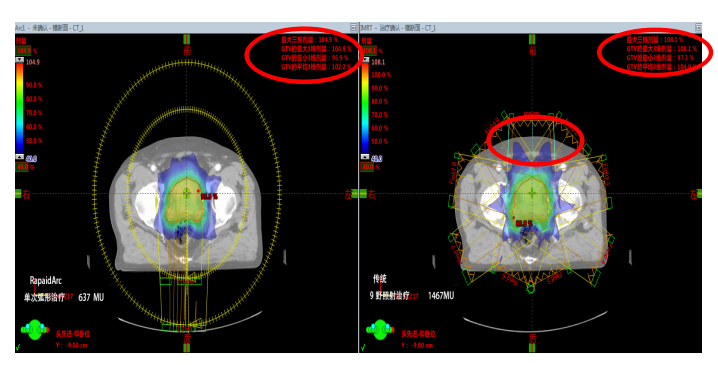

Rapid Arc(快速旋轉(zhuǎn)容積調(diào)強(qiáng)治療技術(shù))使治療時(shí)間的充分減少帶來(lái)諸多好處。首先,病人的耐受力是有限的,治療時(shí)間的縮短可以提高病人的舒適度。其次,是人體內(nèi)部器官的持續(xù)運(yùn)動(dòng),治療時(shí)間的縮短可以減小誤差提高治療的精度跟可靠性。下面以一名前列腺癌患者治愈過(guò)程為例:

1.出色的劑量分布:傳統(tǒng)9野照射治療需出1467MU而RapidArc只需637MU。在確保達(dá)到優(yōu)化劑量分布的前提下,使得機(jī)器跳數(shù)達(dá)到最?。籖apidArc相比于傳統(tǒng)動(dòng)態(tài)調(diào)強(qiáng)具有更均勻的劑量跌落和更低的最大劑量的優(yōu)勢(shì)。

2.出色的放療質(zhì)量:更少的漏射線、散射線,對(duì)患者正常組織和危及器官提供更好的保護(hù),靶區(qū)適形度更好、劑量更飽滿。